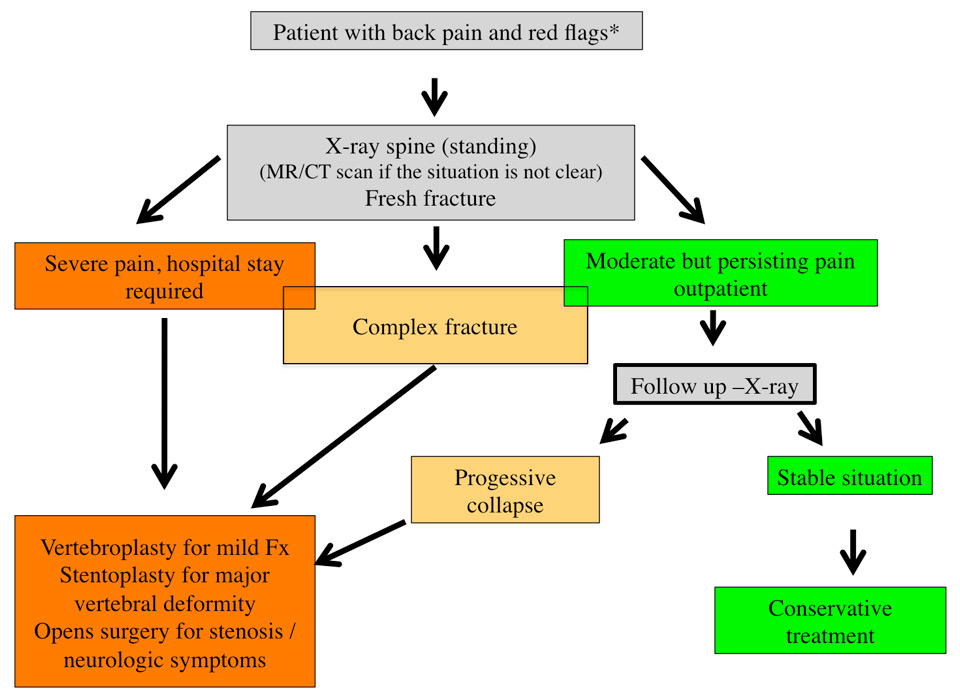

Treatment rationale for osteoporotic vertebral fracutes

Although the majority of vertebral fractures can be treated conservatively it is necessary to avoid complications associated with these fractures. An overview for patient assessment is shown in (fig. 4). This algorithm provides a rationale for differentiation between stable/benign fractures and potentially unstable lesions. Some fracture types have a morphological pattern (complex fracture types) such that surgery is needed from the outset. These are often “traumatic” fractures in the osteoporotic patient. Generally speaking one should assess patients at risk for a possible fracture with a normal (standing) X-ray of the spine section of interest. It is recommended that an x-ray be repeated after one to two weeks if patients continue to have severe pain. In the case of further height loss a surgical procedure should be considered. By this means it is possible to control the pain on the one hand and to avoid a further collapse of the fractured vertebral body on the other. If there is major height loss at this stage the use of a stent allows restoration of the vertebral height. (fig. 6)

Figure 4

Algorithm for the assessment and treatment of patients with osteoporotic vertebral fractures: Patients presenting with acute, severe back or low back pain and a risk profile (red flags) age >65, history of previous fractures, renal disease, steroid medication, BMI <20 etc.) should undergo an imaging study. The investigation of first choice remains a standing X-ray of the region of interest in two planes. If there is any uncertainty an MRI or CT scan can further differentiate between old and new fractures and provide a more detailed impression regarding the exact type of lesion and allow to differentiate between a simple compression type fracture or a complex lesion. The comparison of a standing film with an investigation taken in supine position is helpful for detecting a mobility in the fractured vertebra. Based on clinical findings and the results of the imaging studies one can decide the further treatment. Patients who need hospital admission due the severity of pain or patients with complex lesions should be referred for an early surgical intervention. The majority of patients will remain outpatient. For them it is important to monitor the clinical course and if there is persisting pain or a high risk situation based on their history a follow up X-ray is mandatory in order to check for further height loss of the fractured vertebra or new fractures. If so, again a surgical intervention should be considered. Patients with a spinal stenosis and neurological symptoms usually need an open surgical procedure with decompression and stabilization.